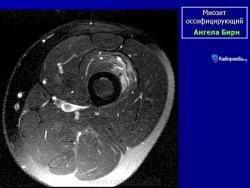

Рентгенологические признаки однотипны для всех форм оссифицирующего миозита; плотный рисунок периферической и менее плотный центральной части повреждения.

При компьютерной томографии визуализируется кальцификация гетеротопической кости, которая продвигается от наружного края образующегося узла в центр.

Рентгенологические признаки однотипны для всех форм оссифицирующего миозита; плотный рисунок периферической и менее плотный центральной части повреждения.